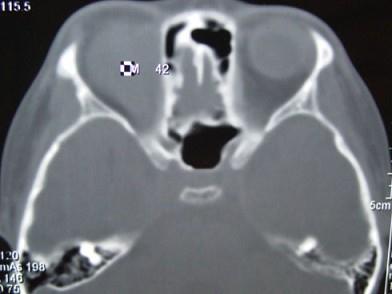

问题 男,12岁,有脓涕数年,发热约十天,伴右眼球向外下突出,CT如图,应诊断为 ( )

选项 A、眼型Graves病 B、肌炎型炎性假瘤 C、骨髓炎 D、骨膜下脓肿 E、转移瘤

答案 D